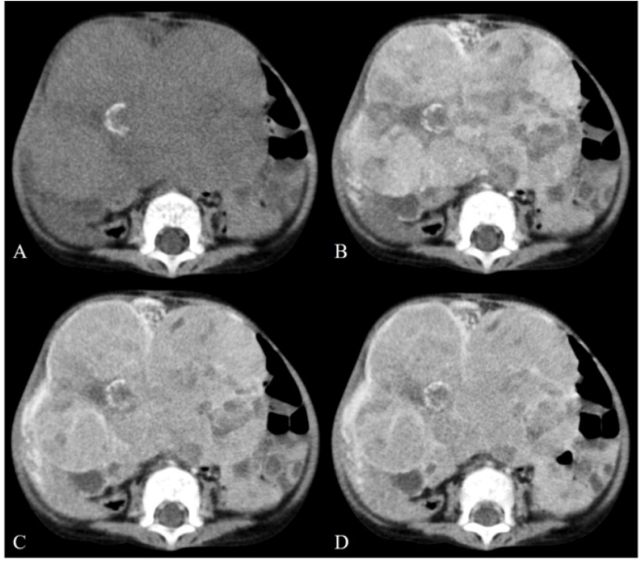

3 year old boy with a large heterogeneous hepatic mass with calcifications, consistent with PRETEXT IV hepatoblastoma.